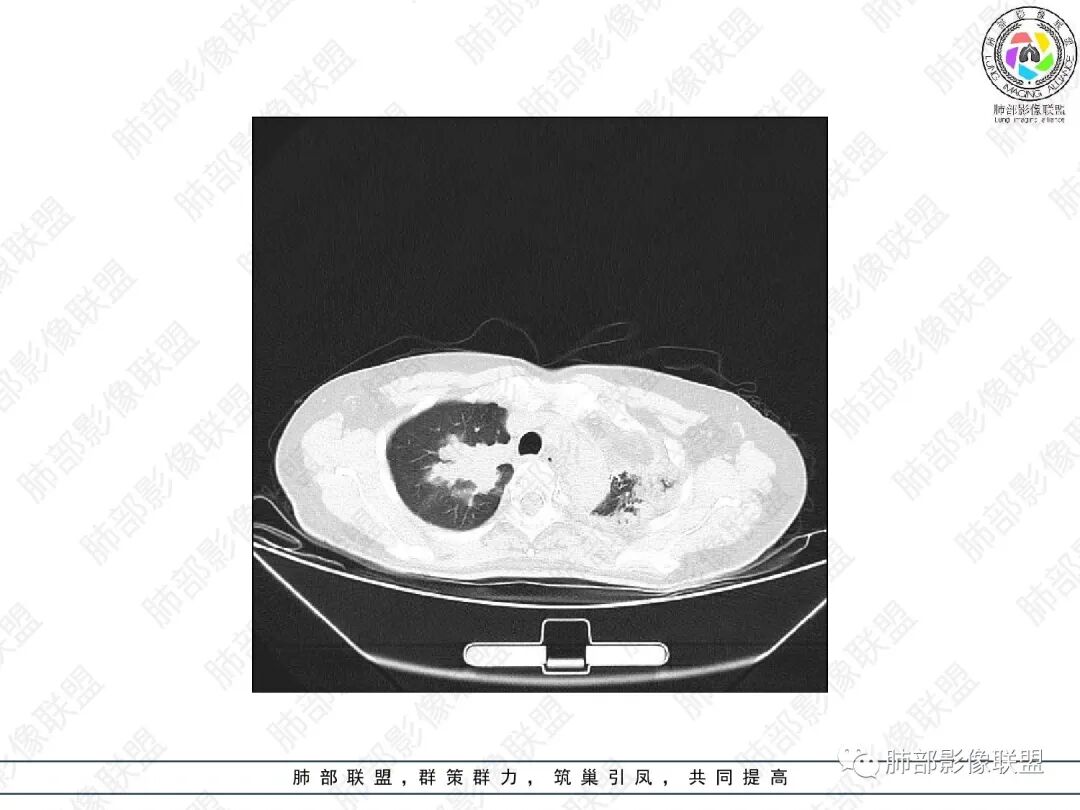

1.中年女性,主因“咳嗽、咳痰半年余”入院,既往史:8年前因左肺病在外院变行左肺叶切除术,诉术后抗结核治疗1年,具体病理等不详。实验室IGE显著增高。

2.胸部CT:右肺上叶及中叶不规则块状影,沿支气管走行方向指套样影,支气阻塞湖嵌塞,腔内可见高密度影。灶周可见磨玻璃,外围见结节影及树芽征。左肺体积缩小,见不规则条索影、胸膜增厚,纵隔牵拉左移。

3.综合分析:结合患者病史及胸部CT主要鉴别ABPA(右肺上叶不规则块影,指套样顺延支气管方向,抗结核治疗1年,肺部病灶仍明显)及继发性肺结核TB(右肺上叶不规则肿块,其可见高密影,边缘模糊,周围卫星灶、树芽征,沿支气管爬行)。

完善气管镜及病理、检验结果(IgE显著增高)等支持ABPA诊断。且给予激素及伊曲康唑治疗后复查胸部CT提示病灶较前吸收,所以诊断明确。